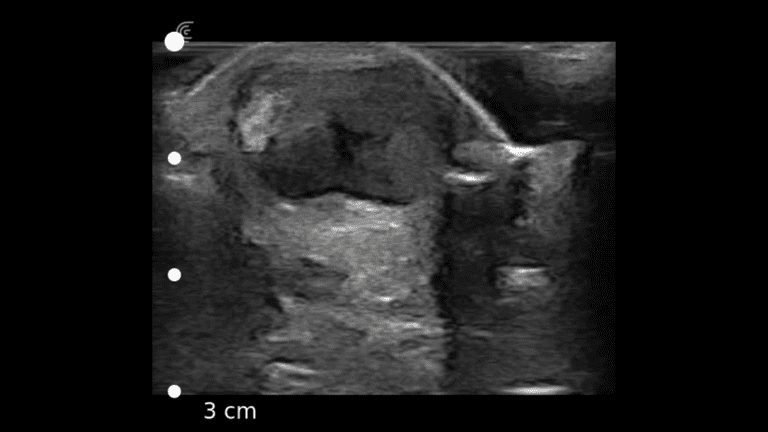

A survey scan of the elbow can identify some of the most common pathologies that cause acute and chronic elbow pain such as tendinosis of the common flexor or extensor tendons, joint effusion, or olecranon bursitis.